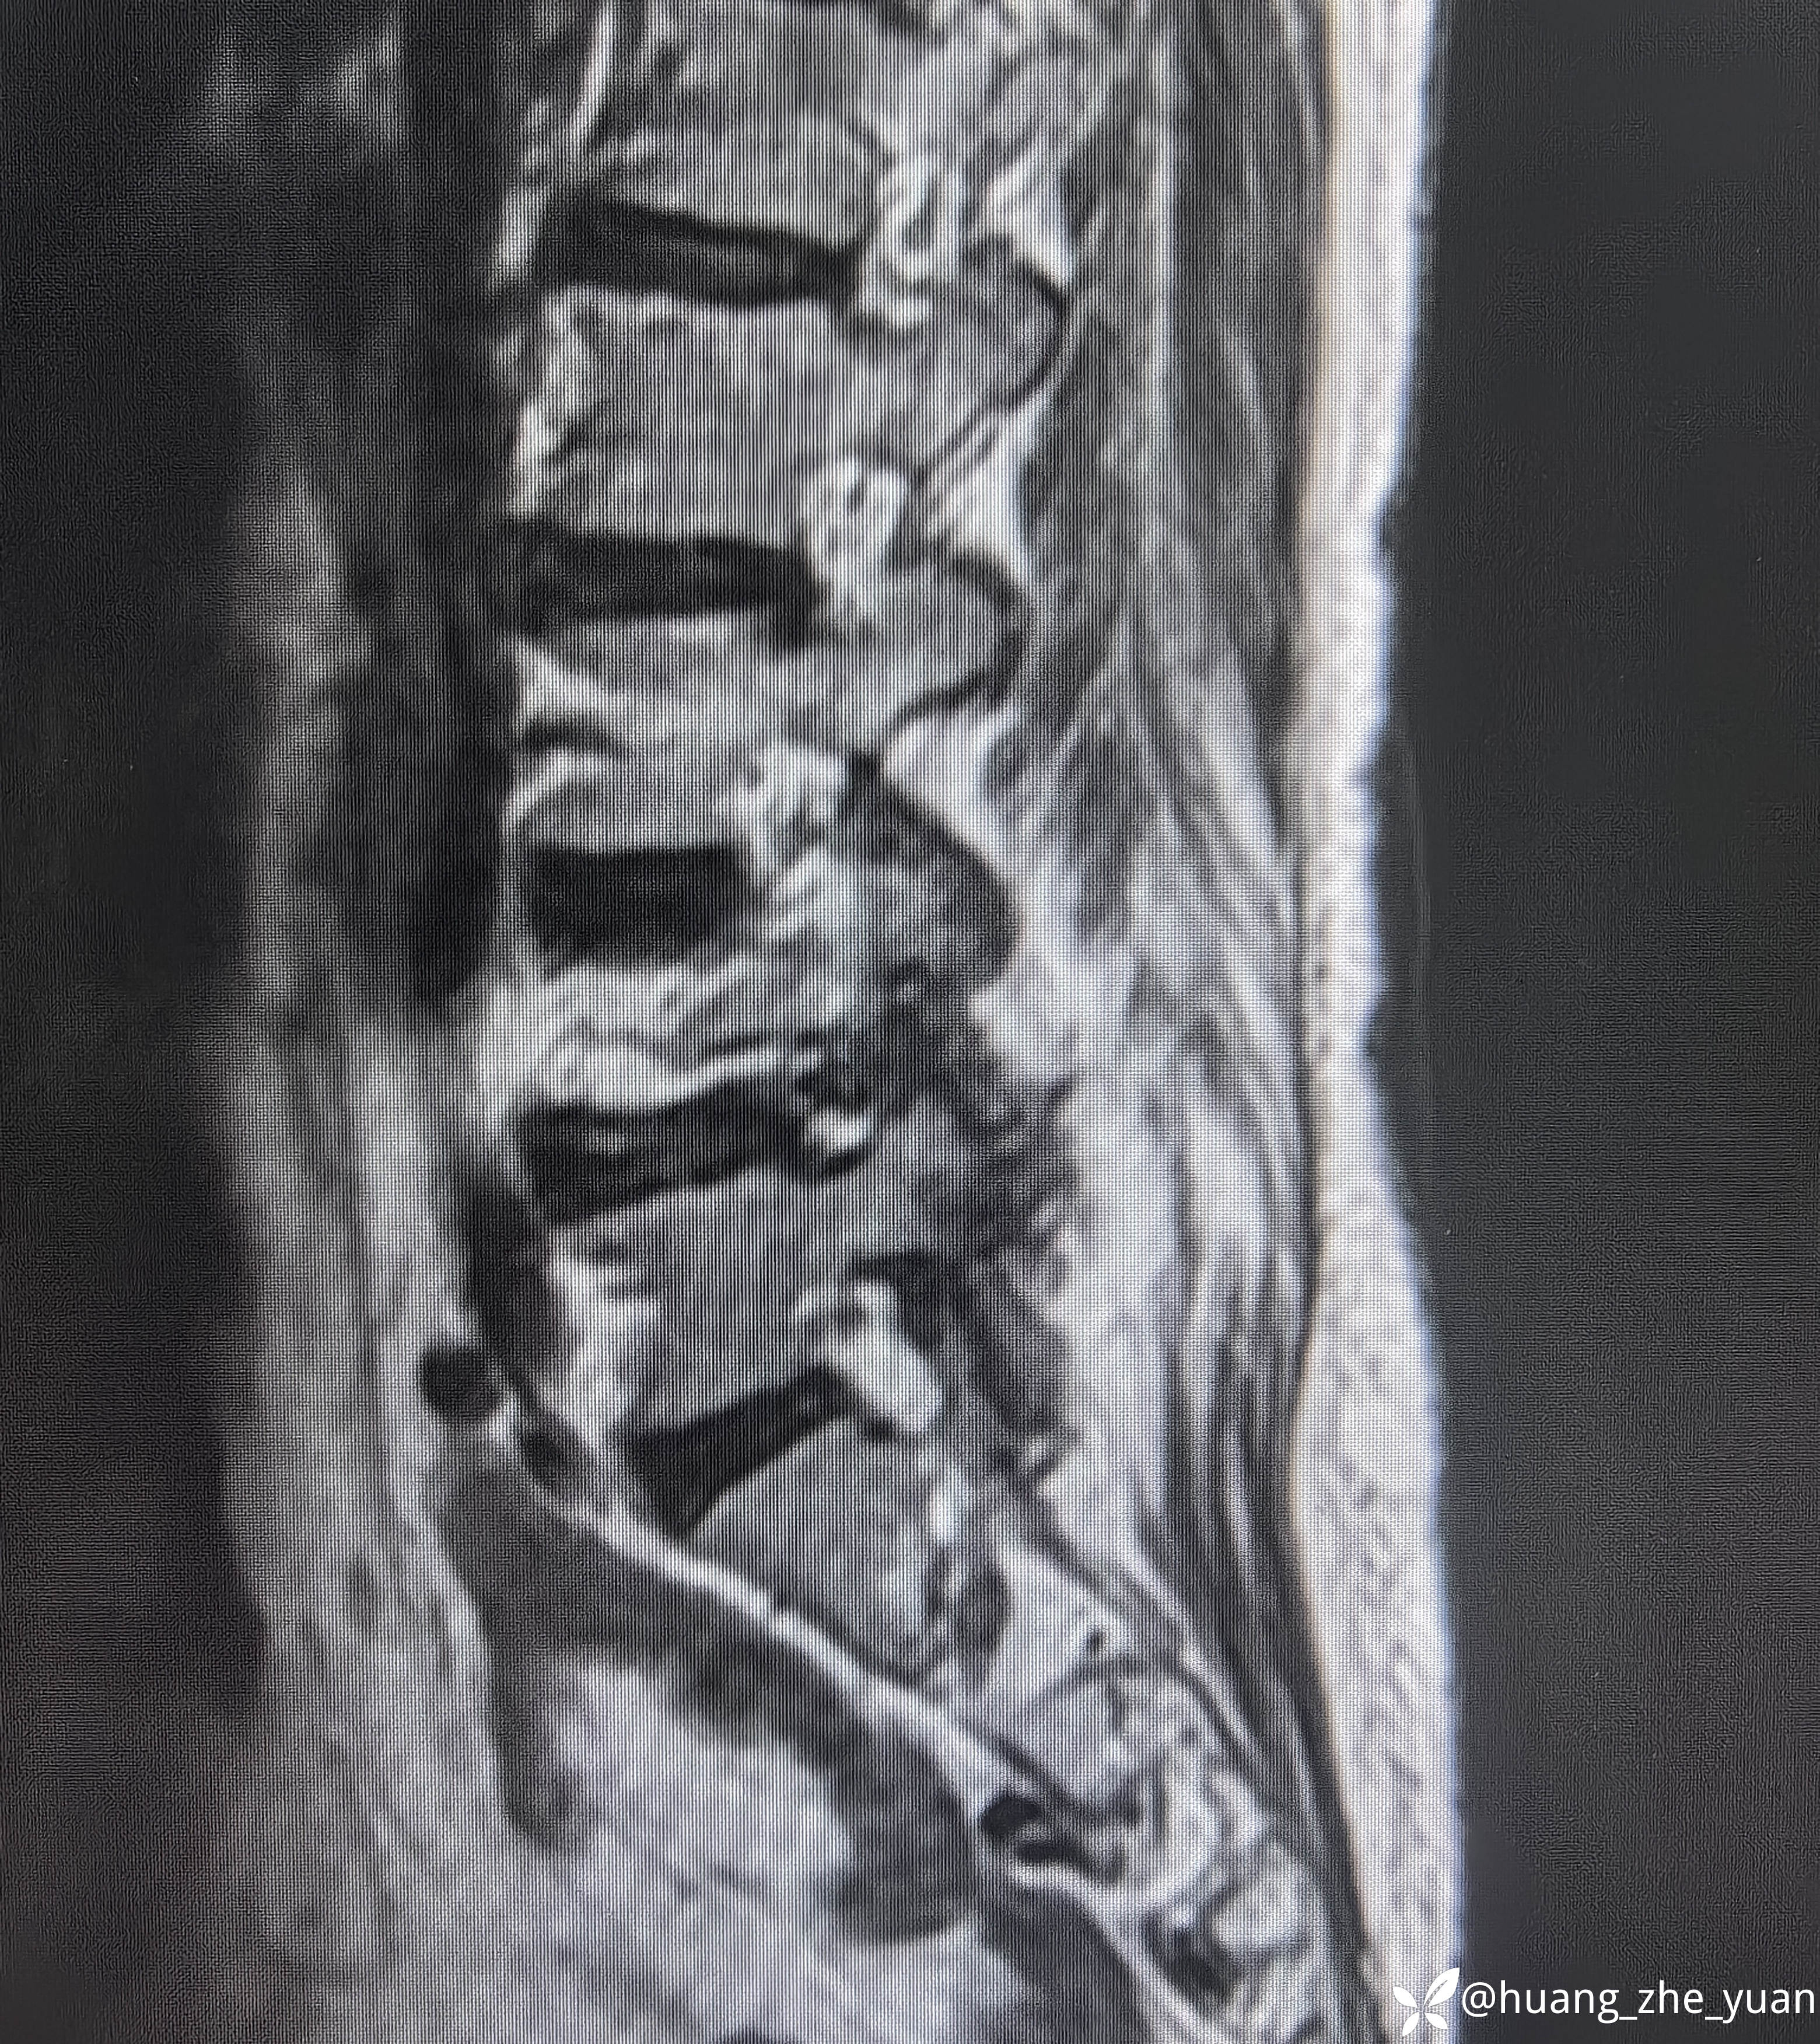

70岁女性,反复右下肢放射痛八个月。合并症:糖尿病,胰岛素泵控制。